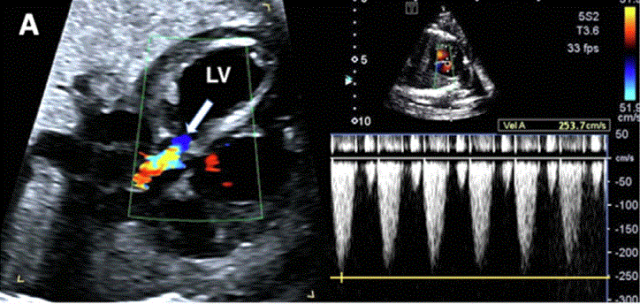

•  评估半月瓣的形态、大小、通畅性和功能,包括使用彩色、PW 和 CW 多普勒,对于诊断和确定病变的严重程度非常重要(图 27)。

图27进展性主动脉狭窄。一例23周胎儿的严重主动脉狭窄,伴有扩张和低动力性左心室(LV)伴心内膜弹性纤维变性。(A) 彩色多普勒显示,主动脉瓣(箭头)开始出现花彩血流(左),频谱多普勒显示阶差为 25 毫米汞柱(右(B) 二尖瓣(MV)流入是单相的,持续时间短(左),二尖瓣反流提示左心室收缩压高(46毫米汞柱压力梯度加左心房压力;右图)。(C)存在逆行主动脉弓流(红色,左)和左至右心房流(红色、右)是预测由于通过左心的流量减少而在妊娠期间发展的进行性左心发育不全的额外发现。(D)LV逐渐变为球状,长度缩短,到36周时不再形成心尖。